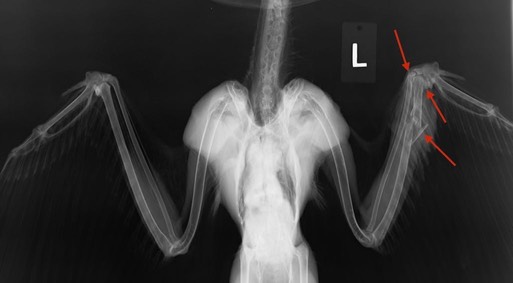

American Kestrel 18-649

Fall and winter are always challenging because most admissions are severely injured. That was the case this past week. Even worse, American Kestrel 18-649 had multiple fractures that were inflicted on purpose, when someone shot him. As is often the case, the injuries were too extensive to repair. There is no sign of lead along the wound channel because the projectile was non-lead and did not fragment.